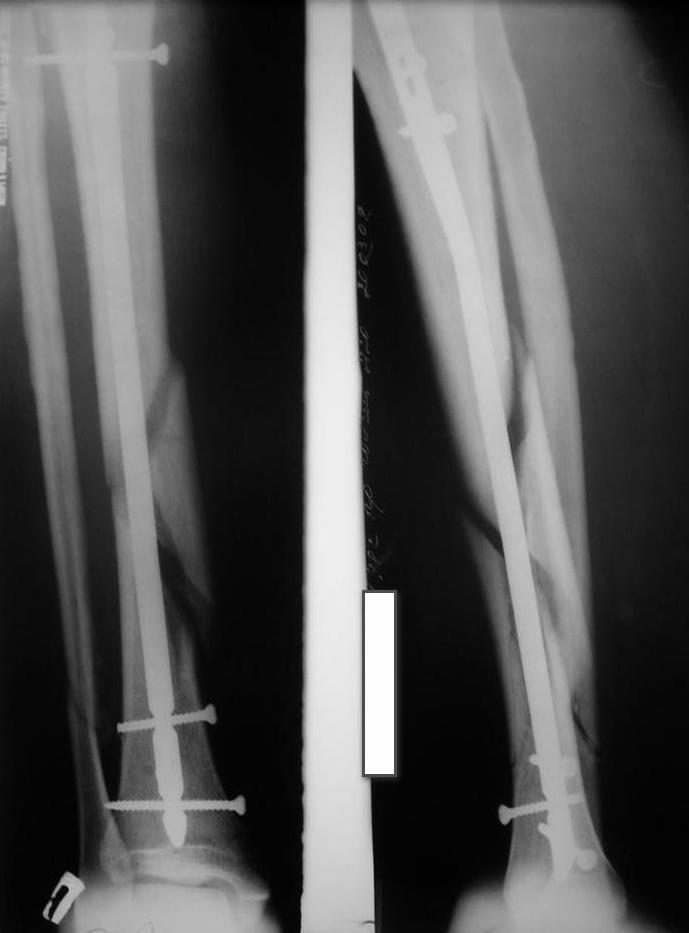

Уважаемые коллеги травматологи подскажите как нам быть и что делать. Думали всем отделением.Несращение оскольчатого перелома костей голени после интрамедуллярного блокируемого синтеза.

У нас был молодой пациент М.(26лет), травма 25 января 2009г, катался на лыжах и получил травму. Поступил к нам в отделение в экстренном порядке. При обследованиии выявлен закрытый винтоообразный оскольчатый перелом правой большеберцовой кости и косой перелом малоберцовой кости на границе средней и нижней трети. Выполнен интрамедуллярный блокируемый синтез большеберцовой кости, оси и длина конечности восстановлена. После операции пациент ходил с полной нагрузкой. Через 3 месяца на контрольных рентгенограммах сращения нет, динамизации не выполняли, так как оскольчатый перелом.(снимки в динамике прилагаются). Посоветуйте, что в данном случае делать наиболее целесообразно?

Остеосинтез, похоже, сделали с перерастяжением, так что динамизировать, наоборот, надо было еще и раньше обычного, недели через 4 после операции.

Да есть диастаз, но скорее от смещения осколка по ширине, а не по длине - по малоберцовой длина нормальна.

>Да есть диастаз, но скорее от смещения осколка по ширине, а не по длине - по малоберцовой длина нормальна

И малоберцовая перерастянута. По большеберцовой видно щель по переднему контуру, промежуточный фрагмент к этой области не имеет отношения.

мы бы подождали с динамизацией еще 6-8 недель

Отсутствие уверенных признаков сращения неделям к 8 - надо динамизировать. Тут уже 3,5 мес., есть щель из-за смещения по длине. Дальнейшее консервирование ситуации тут не решает никаких проблем, а вот создать их может. Динамизация с нагрузкой и диастаз уменьшит, и репаративный процесс "освежит".

Мне кажется, что необходимо выполнить динамизацию, одновременно выполнив остеотомию малоберцовой кости, т.к. у нее консолидация есть. В дальнейшем ходьба с дополнительной опорой и потепенным увеличением нагрузки около 25% в неделю с выходом до полной на 4-й неделе.

Господа,никаких признаков консолидации нет.Если где-то кажется,то это только за счет укладки(все снимки по-моему с разной укладкой).

Я бы сделал так:произвел бы закрытый остеосинтез по Илизарову,не вынимая штифт,с остеотомией малоберцовой кости и одновременно(одномоментно)-операция туннелизации места перелома по Беку.После этого на операционном столе же удалить шурупы из штифта и производить плановую дистракцию.

По-моему, оптимальное решение уже прозвучало дважды: динамизация+остеоклазия(остеотомия) малоберцовой.